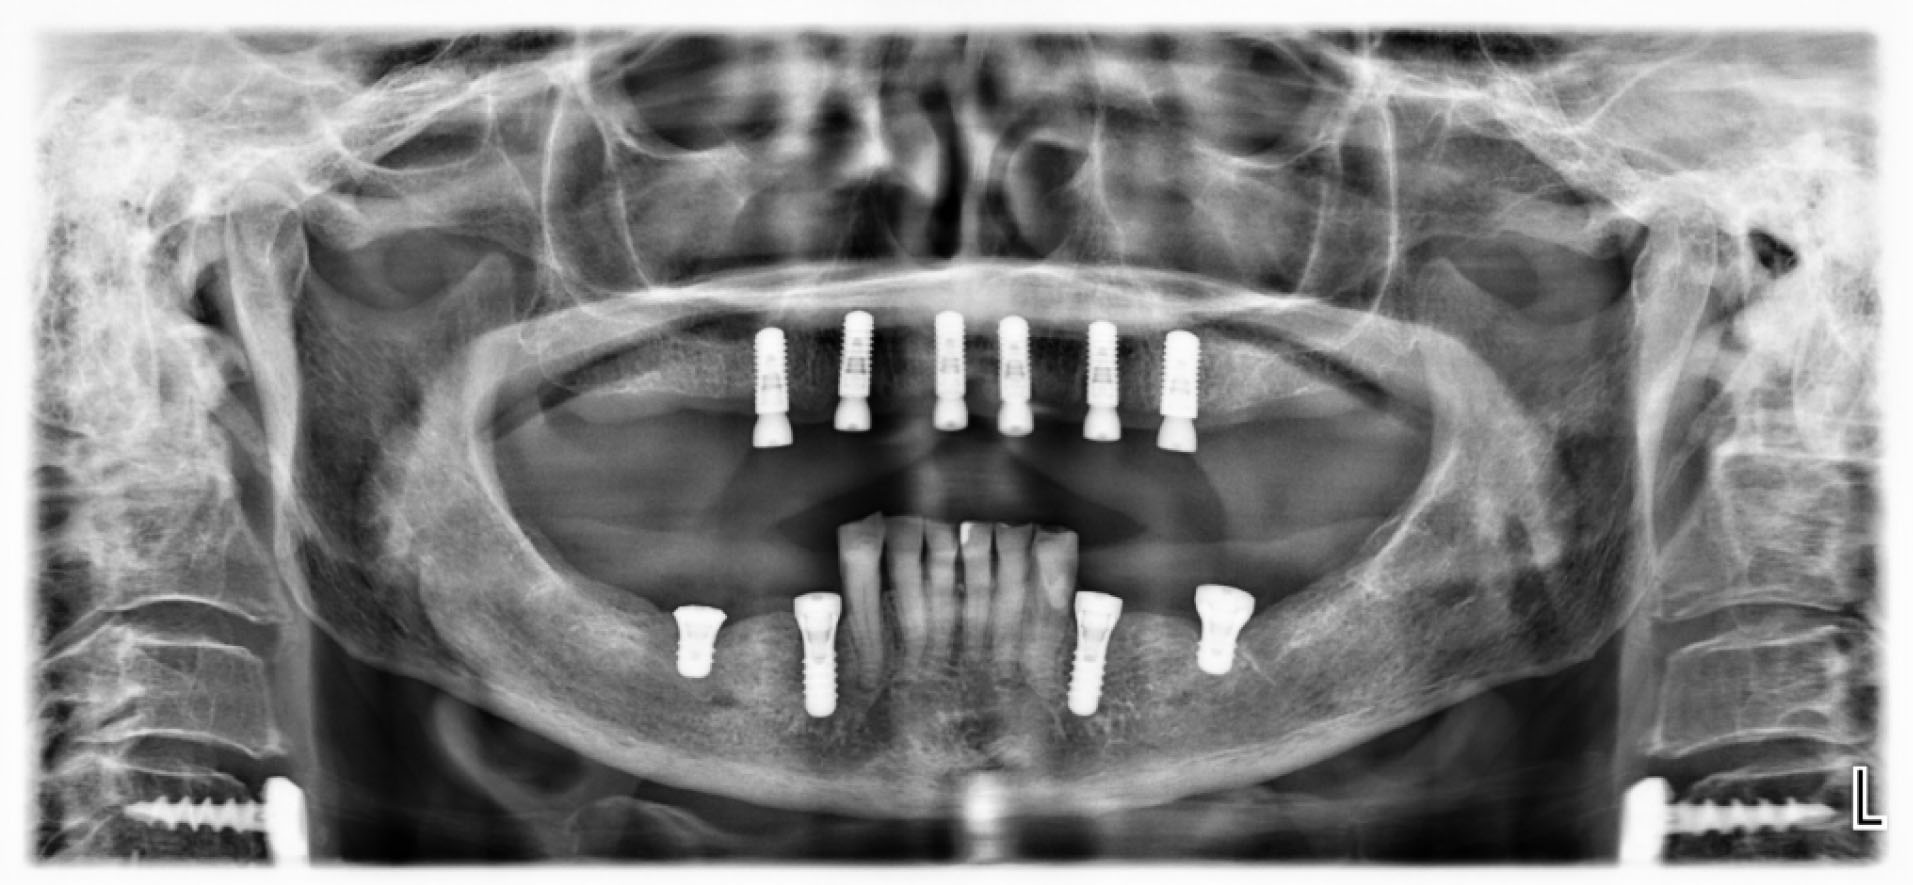

Six implants (five 4.1 x 10 mm and one 4.8 x 10 mm Straumann SLA Bone Level implants) were planned to be evenly distributed in the maxilla so as to minimize the extension of posterior cantilevers, using guided surgery (). Open flap surgery was necessary as the regularization of the edentulous bone would be necessary prior to the implant placement. In the mandible, four Straumann tissue level implants were placed bilaterally to support two ceramic fixed partial dentures ().

joddd-15-115-g004

Figure 4. Panoramic radiograph after osseointegration of implants.